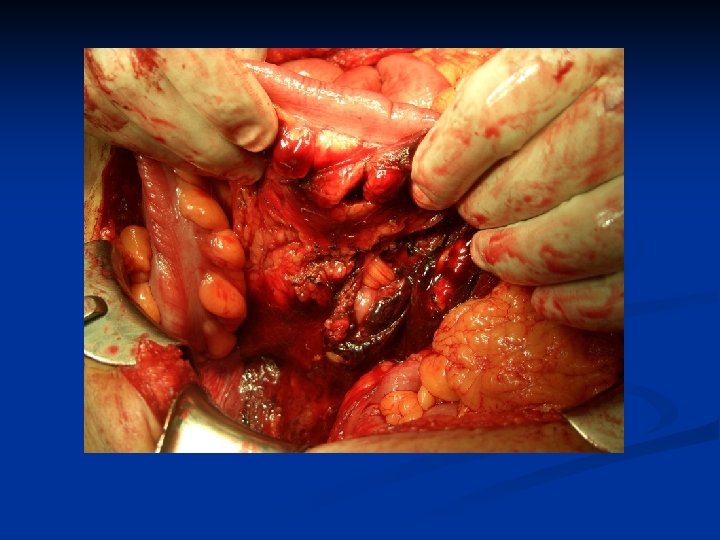

On Route to OR n n ABC Chest x-ray, Pelvis x-ray IV access Resuscitation n n n What is the goal? Group and Match Notify OR, Surgeon, Anaesthesia Request OR equipment Consent Antibiotics

Case 1: Learning Points Recognize Shock n Hemodynamically unstable = OR n Role of FAST, DPL n Permissive hypotension in resuscitation until bleeding controlled n